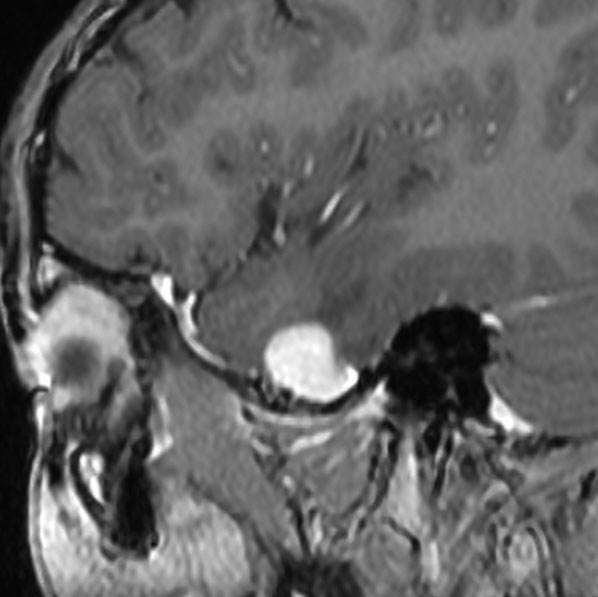

小児の神経節細胞腫 gangliocytoma グレード1(過誤腫のような良性腫瘍)

10才の時に,複雑部分発作(症候性てんかん)で発症しました。吐き気を感じた後に嘔吐して意識が遠くなる(意識減損)という症状であり,側頭葉てんかんです。脳波では左側頭葉に徐波律動がみられました。発作は頻回でしたがカルバマゼピンの投与で抑制されていましたが,MRIで腫瘍が発見されました。

左内側側頭葉グリオーマ mesial temporal glioma と呼ばれる腫瘍です。左の扁桃体,海馬鉤,海馬,海馬傍回に腫瘍が浸潤しています。T2強調画像とFLAIRでまだらな高信号で境界ははっきりしません。mass effectが少なく,増殖増大傾向のある腫瘍には見えないのが特徴です。下段右のように部分的にガドリニウム増強されるのも神経節細胞腫の特徴かもしれません。しかし,神経節膠腫,乏突起膠腫,乏突起星細胞腫(グレード2)なども疑われます。

手術中の脳波モニターでは,棘波が上側頭回の後方(ウェルニッケ領域)に存在し,深部電極刺入で海馬近傍にも棘波がみられましたが,もちろん上側頭回や海馬の切除はしませんでした。扁桃体 amygdala と海馬鈎 uncus の腫瘍部分のみを切除して手術を終了しています。海馬と海馬傍回には腫瘍を残しました。上のMRIは,その後6年経過した後のものですが腫瘍は全く同じ大きさです。抗てんかん薬も止めて,発作は全く生じていません。このような腫瘍は,扁桃体と海馬鉤を摘出することで,発作を完全に止めることができることがあります。ですから,最初の手術では,リスクのある余分な脳切除をしません。